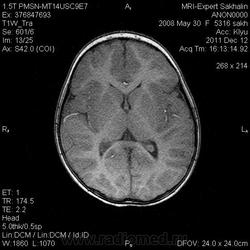

Девочка 3 года.В анамнезе -родовая травма-внутрижелудочковые кровоизлияния 1-2 ст.Задержка психического развития.Со слов мамы, "бывают истерики, хватается ручками за голову, особенно затылочную часть".Как интерпретировать изменения в желудочках, в задних рогах?Ликворную кисту ЗЧЯ отметила.

Здравствуйте! Извините что вклиниваюсь в вашу дискуссию. В дополнение ко всему сказанному мне показалось что для трехлетнего ребенка желудочки несколько великоваты, больше слева. Ликворные пространства не симметричны, опять больше слева. В складочках мозга мелкие, пока, кисточки. Может быть попробовать исключить церебральный арахноидит? Пункцию делали?

Коллеги, в рамках ликбеза: а такое (некоторое) расширение субарахноидального пространства (не вполне характерное для 3-летнго ребенка), расценивается как гидроцефалия (заместительная, открытая, последствие ишемически-гипоксического синдрома) или нет?